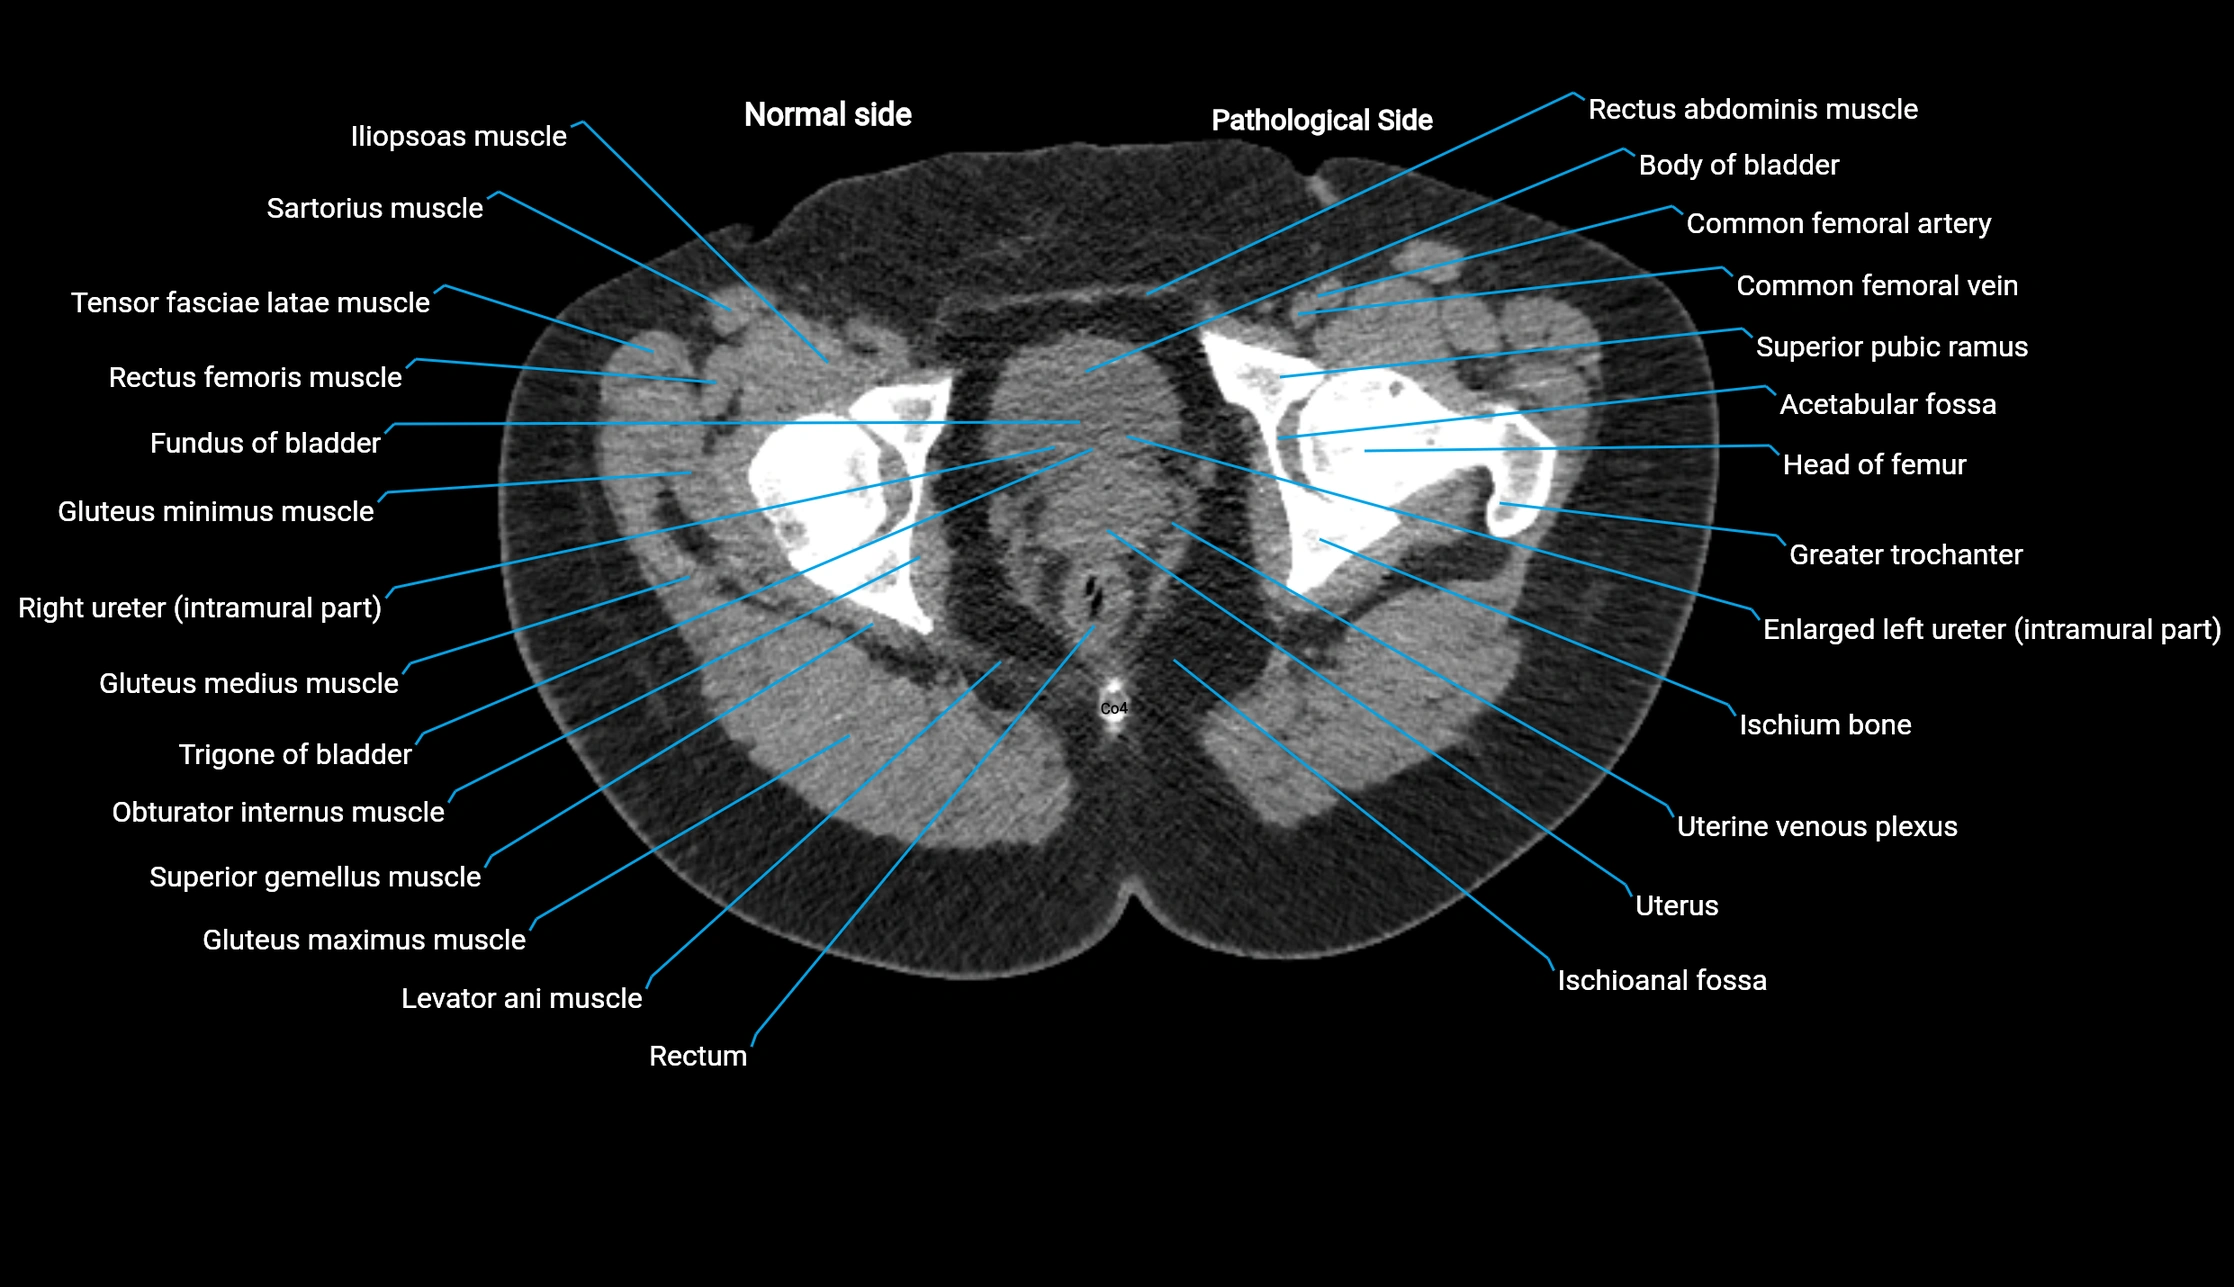

CT image

image